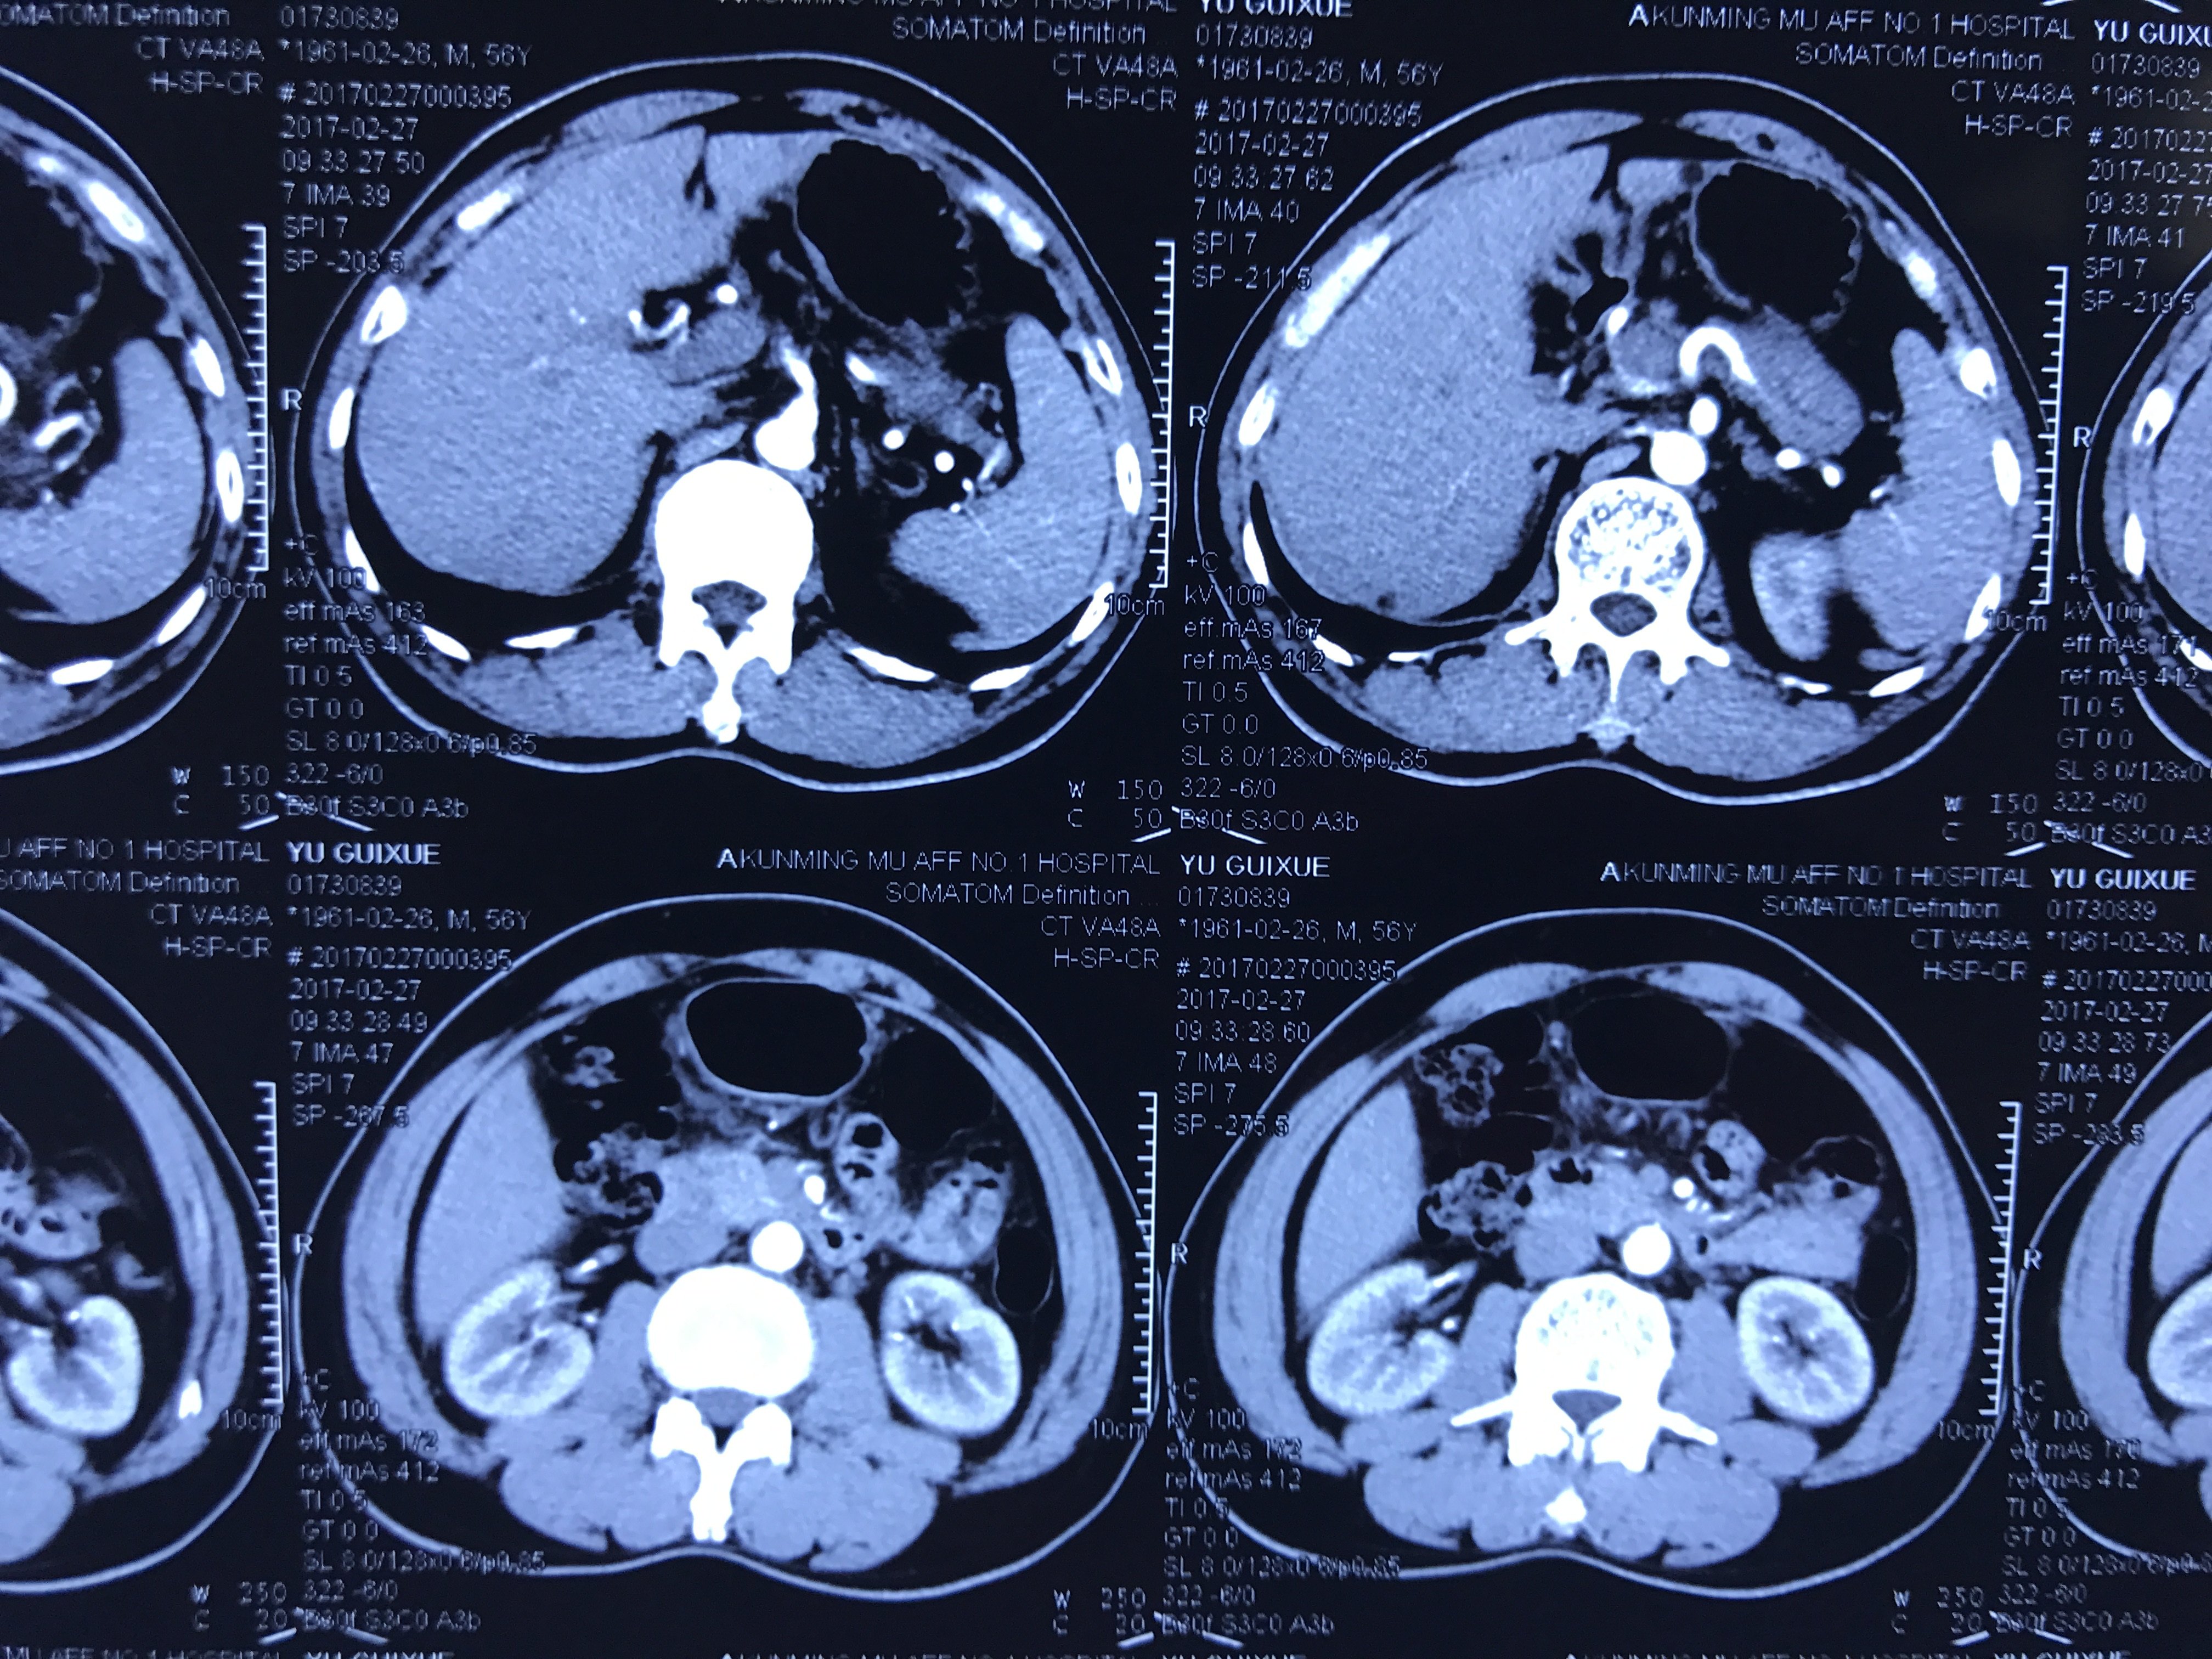

这里主要指的是CT、核磁共振等特殊检查的片子。

首先要解释的是一个是您拿到的影像片子,另一个是您拿到的报告单。

①报告单是放射科医生做出检查后给出的提示是总体性的且有一定法律效应的结论。

②我们专科医师看片子需要根据专科的角度去判断片子中疾患的部位、大小、血液供应、周围粘连、目前疾患的进展、甚至手术方案、病情的预后都已经了然在心中了。

所以完整的把检查资料传到医生的手中是非常关键的。

如何正确的把拍的片子发给医生看!

一般的报告就不再说了,正常拍摄就可以,我说的是片子应该怎么拍,一般是1-4小张拍一次,如下图:

下面看看直接无法直视的!